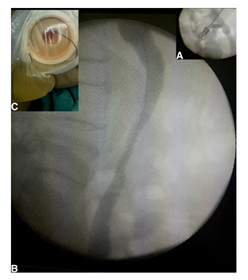

The patient is in a strict lateral position. After administration of 10 ml xylocaine, a kidney puncture is made under fluoroscopic guidance using a 22G Chiba needle (Figure 1A). Opacification of the collecting system permits to localise and observe the severity and length of the stricture. A second puncture is made using an 18G Chiba needle directly in the upper calyceal group, sometimes above the 12th rib. A hydrophilic 0.35-mm guide wire is introduced through the needle into the renal pelvis and ureter in antegrade fashion until it reaches and passes through the stricture (Figure 1B). The guide wire exits then through the ileostomy (Figure 1C). A 5F, 6F, 7F, and 8F ureteral stents are inserted on the guide in retrograde fashion to dilate the stenosis. Finally, a 7F single-J stent was placed and left in place (Figure 2). The patient remains under observation for 4hours and is then discharged. The stent is replaced every 9months in a retrograde manner through the ileostomy and under fluorescence guidance, on an outpatient basis.

Figure 1 A: Antegrade pyelography after kidney picture in a patient with solitary kidney; B: Guide wire through the ureterointestinal stricture passes through the stricture; C: the guidewire exits through the ileostomy.